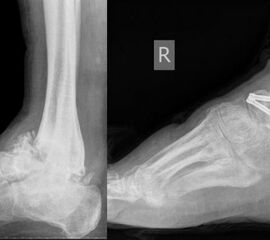

- Operative Behandlung von Druckstellen durch Fehlstellungen/Instabilität des Rückfußes bzw. Sprunggelenk

Eine weiterer typischer Verlauf eines Charcot Fußes betrifft die Zerstörung der Bänder und des oberen Sprunggelenks. Der Fuß knickt dabei nach innen, manchmal auch nach außen weg. In Schuhen kommt es meist zu Druckstellen im Bereich des Knöchels. Teilweise ist das Sprunggelenk ist so instabil, dass Laufen nicht mehr möglich ist. Oft sind hier die Möglichkeiten einer konservativen Therapie mit Polsterung/Schuhversorgung nicht mehr ausreichend. Kann der Fuß von außen nicht mehr ausreichend stabilisiert werden, ist eine operative Stabilisierung der abgekippten Gelenke mit Platten und Schrauben notwendig um wieder einen belastbaren Fuß zu erreichen.